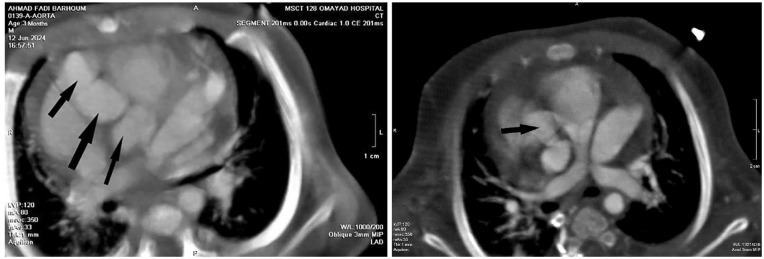

Kawasaki disease (KD), a febrile vasculitis primarily affecting young children under 5, is commonly associated with coronary artery complications. This report describes the case of a 2.5-month-old infant presenting with a persistent 15-day fever, initially misidentified as pharyngitis and otitis media. Laboratory tests indicated significant leukocytosis, thrombocytosis, and increased C-reactive protein (CRP) levels. Echocardiography revealed coronary artery dilation and pericardial effusion, confirming a KD diagnosis. The infant received intravenous immunoglobulin (IVIG) and high-dose aspirin, which resolved the fever. Symptom recurrence necessitated additional IVIG and corticosteroid treatment. Subsequent imaging showed ongoing coronary dilation, emphasizing the risk of lasting vascular complications. This case underscores the diagnostic challenges of KD in infants, especially those with atypical presentations. Prompt diagnosis and treatment are critical to prevent serious complications such as coronary aneurysms. Healthcare providers should consider KD in infants with prolonged unexplained fevers to improve prognosis and minimize heart-related risks.